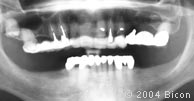

101. |

第五次手术后的X光片。 |